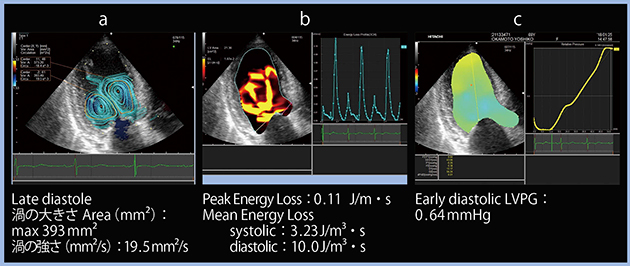

Cace 2: 60歳代,男性,心不全歴あり

本症例は,心エコーにて左室の収縮力は良好であり,EFは60%程度であった。また,ガイドライン1),2)では,左室の障害が疑われる症例に対して,左室拡張能の指標であるE/e’(中隔側,側壁側の平均)>14,TRV>2.8m/s,LAVI>34mL/m2の3項目を評価するよう規定しており,2つ以上が陽性の場合は左房圧上昇があるとしている。本症例は,平均e’は8cm/sと保たれているが,E/e’が14,TRVが3.2 m/s,LAVIが62mL/m2と3項目が陽性であり,左房圧上昇と判断できる。また,左室・左房ストレインを計測したところ,GLSは−16.4%,LA strainは22.1%であり,健常例と比べて低下していた。

続いて,VFMの評価であるが,流線表示にて渦を見ると,拡張後期の渦の大きさは最大393mm2,渦の強さは19.5mm2/sと,健常例と比べて大きかった(図2 a)。エネルギー損失は,Peak Energy Lossが0.11J/m・s,Mean Energy Lossは収縮期が3.23J/m3・s,拡張期が10.0J/m3・sと明らかに大きかった(図2 b)。一方,LVPGは,early diastolic LVPGが0.64mmHgと低かった(図2 c)。

図2 HFpEFにおけるVFMのパラメータ

a:流線表示(渦の評価) b:エネルギー損失 c:LVPG